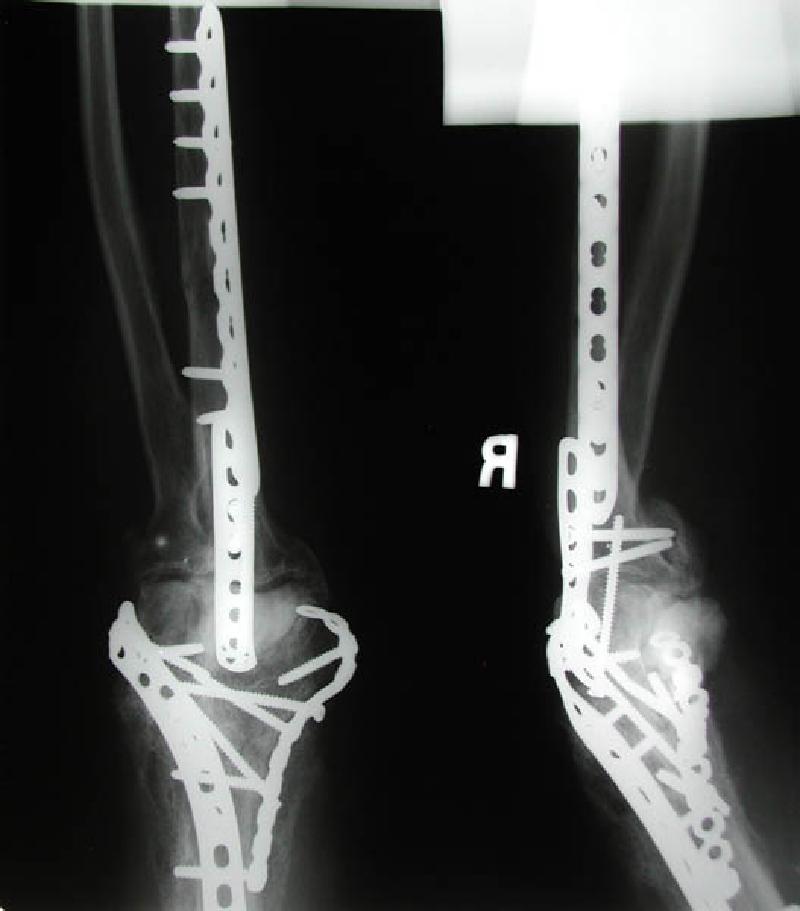

Front and side views of Marla's right elbow before her April 22nd elbow replacement surgery. The screws and plates were emplaced during the first re-construction post-trauma in December 2002. The entire infrastructure was surrounded by and interwoven with excess bone build-up, a common side effect of joint trauma coincident with head trauma. This excess bone had to be removed during her elbow replacement surgery.